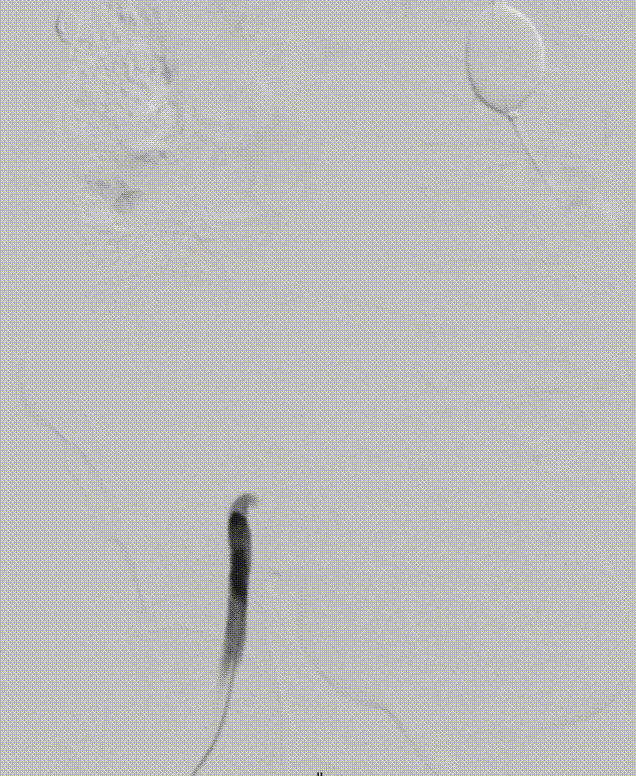

5. 经右侧股总送入泥鳅,再通过泥鳅输送另一个MOB球囊在原球囊远端,尝试将近端的球囊回收,同时展开远端球囊,在远端球囊被造影剂完全展开贴合血管壁以前,将原MOB球囊撤出。

gore医疗怎么样「漫腹精论」髂合时宜 精益求精——双MOB球囊导管辅助腹主动脉覆膜支架急诊治疗破裂巨大髂动脉瘤_https://www.jmylbn.com_新闻资讯_第16张

gore医疗怎么样「漫腹精论」髂合时宜 精益求精——双MOB球囊导管辅助腹主动脉覆膜支架急诊治疗破裂巨大髂动脉瘤_https://www.jmylbn.com_新闻资讯_第17张